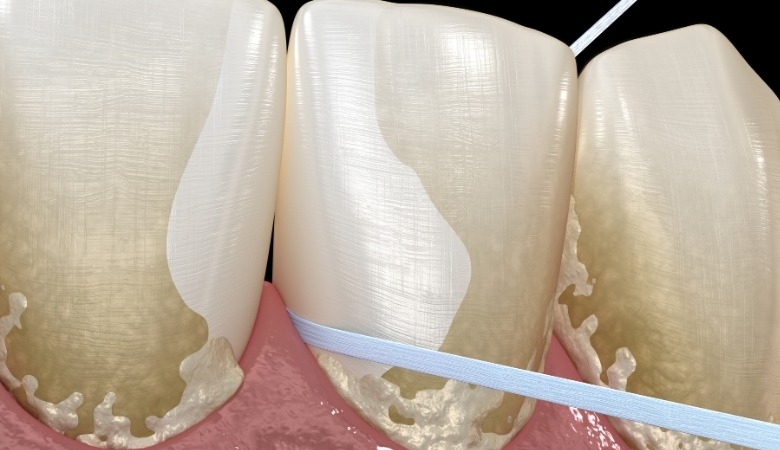

Khi mảng bám không được loại bỏ thường xuyên thông qua việc đánh răng và sử dụng chỉ nha khoa, các khoáng chất trong nước bọt, đặc biệt là canxi phosphate, sẽ dần dần thấm vào mảng bám. Quá trình này dẫn đến sự vôi hóa, khiến mảng bám mềm trở nên cứng và bám chắc vào bề mặt răng, tạo thành cao răng.

- Ngay sau khi ăn khoảng 15 phút: Một lớp màng mỏng vô khuẩn gọi là pellicle sẽ hình thành trên bề mặt răng, chúng có vai trò như một lớp bảo vệ ban đầu cho men răng nhưng cũng tạo điều kiện thuận lợi cho vi khuẩn bám vào. Các vi khuẩn trong miệng, bao gồm cả vi khuẩn có lợi và vi khuẩn gây hại, sẽ bắt đầu tích tụ trên lớp pellicle, kết hợp với các mảnh vụn thức ăn còn sót lại, đặc biệt là đường và tinh bột, để tạo thành mảng bám răng. Mảng bám lúc này vẫn còn mềm và có thể được loại bỏ bằng cách chải răng đúng cách.

- Trong vòng khoảng một tuần: quá trình vôi hóa sẽ bắt đầu diễn ra nếu các mảng bám không được làm sạch kỹ lưỡng, các khoáng chất như canxi và phosphate có trong nước bọt sẽ lắng đọng vào mảng bám, khiến chúng trở nên cứng dần. Quá trình này diễn ra từ từ, từ lớp ngoài vào bên trong của mảng bám.

- Sau một thời gian dài: mảng bám đã vôi hóa hoàn toàn sẽ trở thành cao răng, bám rất chắc vào bề mặt răng và nướu. Lúc này, cao răng đã trở thành một nơi trú ẩn lý tưởng cho vi khuẩn, tạo điều kiện cho chúng tiếp tục phát triển và gây ra các vấn đề răng miệng khác.

Quá trình hình thành cao răng diễn ra trong một thời gian dài do thói quen vệ sinh răng miệng không đúng cách (Nguồn: Internet)